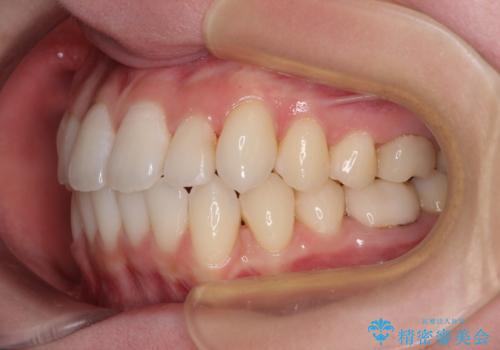

ワーキングホリデー前にきれいな歯列に

- 2、3年後にワーキングホリデーで海外に行くため、その前に歯列やむし歯をきれいにしたいとのことで来院された患者様です。

抜歯の必要な右上の奥歯は事前に抜歯をし、インビザラインにて上下歯列を整えることとしました。

矯正治療後半に奥歯の補綴治療が必要な歯にはオールセラミッククラウンを装着し、インビザラインで最終的に仕上げることとしました。

海外に行く前に口腔内環境を整えることができ、患者様には大変満足していただきました。